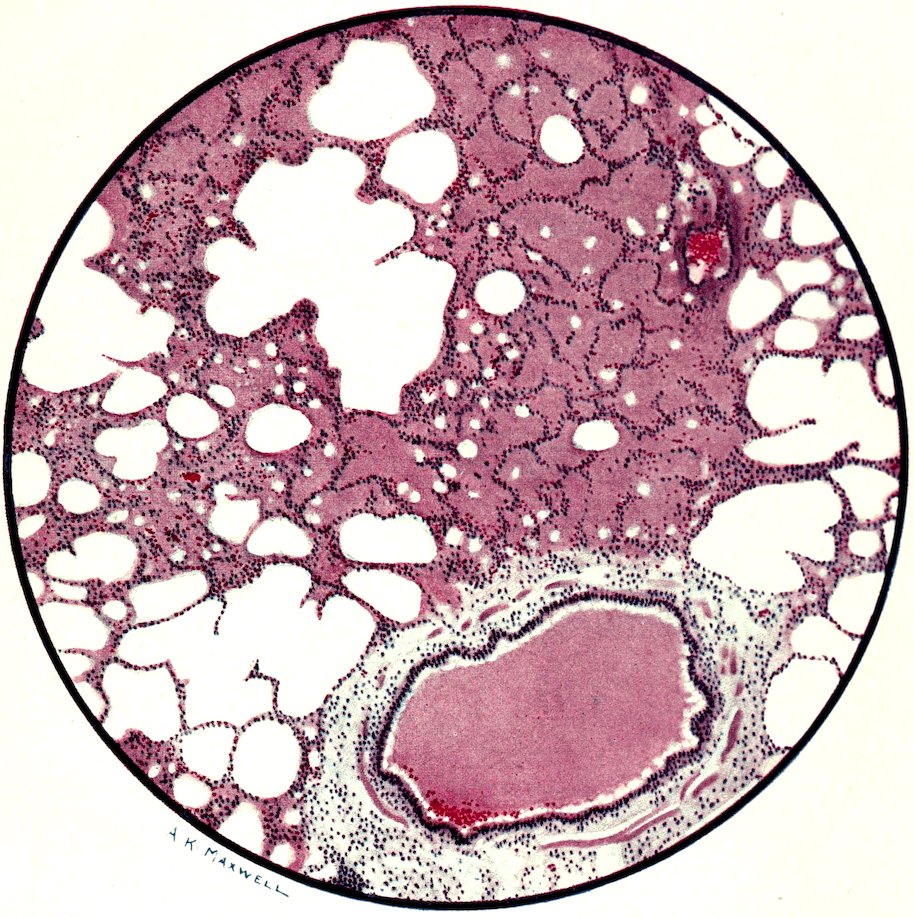

PLATE NO. I

Microscopic section of human lung from phosgene shell poisoning. Death at the nineteenth hour after gassing.

The piece of lung shown is almost entirely useless for aeration of the blood. Most of the pulmonary alveoli are filled with oedema fluid, and the walls of the air sacs are burst asunder in many places. The rounded edges of these torn walls can be recognized both in the areas of emphysema and in the parts that are flooded with oedema fluid. The bronchus also is filled with oedema fluid, but it should be noted that its lining epithelium is intact and pus cells have not accumulated in the secretion. The blood vessels of the alveolar network are congested; and intravascular thrombosis is frequently found in these smaller vessels, though it is not actually shown in the area of this section.

The main changes in the lung are:

Congestion, and occasional thrombosis, of the network of pulmonary blood vessels.

Abundant outpouring of inflammatory oedema fluid both into the tissues and into the air spaces of the alveoli and bronchi.

Disruptive emphysema of the weakened lung tissue.

The result of these changes is that the blood circulation through the lungs is impeded, and the respiratory exchange of gasses between the blood and the air in the lung is seriously diminished. The gassed man is in danger of death by asphyxia so long as his lung is drowned in oedema fluid.

From the third day onwards the oedema fluid is reabsorbed or expectorated, and the lung soon resumes its functions. Bronchopneumonic complications may develop from secondary infections, but they are not very common.

The recovery of the lung, even after severe gassing appears to be functionally good. In the earlier stages of convalescence there may still be signs of persisting oxygen want, so that tachycardia with excessively rapid respiration is the result of even slight physical effort. Later these disabilities vanish. The microscopic examination of lungs in these stages of recovery has not been made.